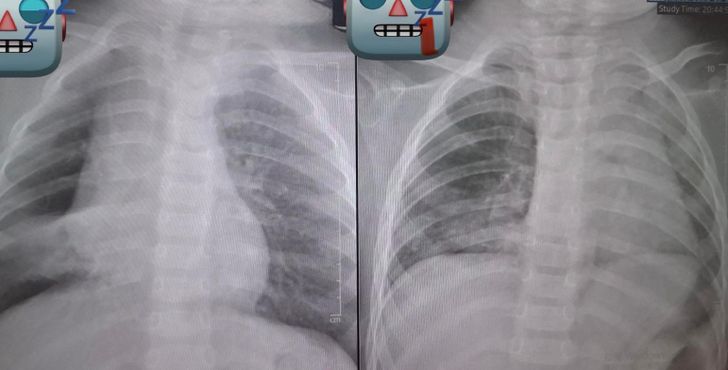

เหตุการณ์นี้เกิดขึ้นเมื่อเด็กถูกส่งตัวมายังโรงพยาบาลด้วยอาการไอและมีเสียงหายใจวี้ดๆ (Wheezing) หลังจากที่คุณยายป้อนถั่วลิสงให้ทานเมื่อ 3-4 วันก่อนหน้านั้น แม้อาการแรกเริ่มจะไม่ชัดเจน แต่เมื่อเอกซเรย์กลับพบข่าวร้ายว่า "ปอดเริ่มแฟบ" (Lung Collapse) เนื่องจากมีสิ่งแปลกปลอมอุดกั้นทางเดินหายใจ

ทีมแพทย์นำโดยสามีของคุณหมอเลี่ยว ต้องรีบทำการส่องกล้องหลอดลมเพื่อคีบเอาถั่วลิสงออกมา แต่ทว่าไม่ง่ายอย่างที่คิด เพราะถั่วเม็ดนั้นติดค้างมานานหลายวันจนมีเนื้อเยื่ออักเสบงอกขึ้นมาหุ้ม (Granulation Tissue) ทำให้ถั่วติดแน่นในหลอดลมที่เล็กจิ๋ว ทีมงานต้องใช้ความพยายามอย่างหนักเกือบ 2 ชั่วโมง กว่าจะจับเจ้า "ถั่วเต้นระบำ" ที่ลื่นไหลไปมาออกมาได้สำเร็จ